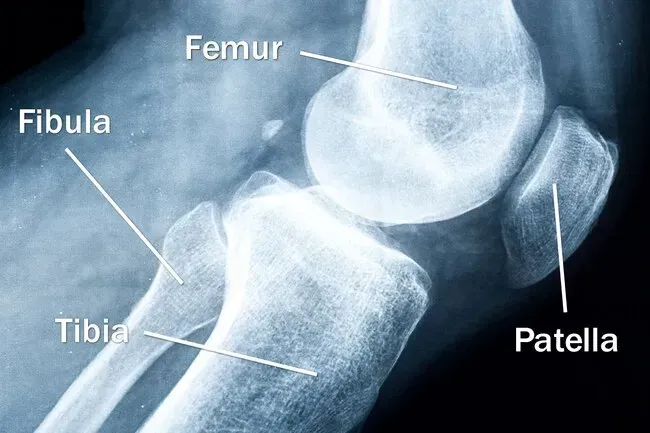

Knochen

Vier Knochen treffen sich, um Ihr Knie zu bilden: Ihr Oberschenkelknochen (Femur) Shinbone (Tibia) Der kleinere Knochen, der neben ihm (Fibula) und Kniescheibe (Patella) läuft. Jeder von ihnen könnte knacken (Bruch) oder brechen. Oder ein kleines Stück kann abbrechen. Sie können auch eine dieser Knochen, insbesondere in Ihrer Kniescheibe, nicht mehr zu plündern oder zu verschieben.